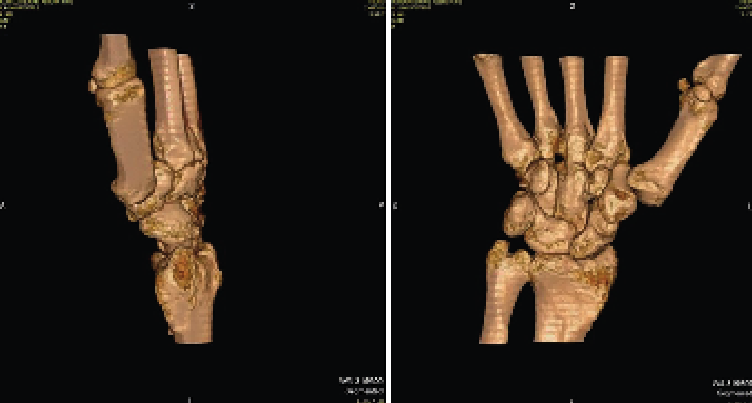

Se solicitan estudios de imagen. En primer lugar, rayos X de muñeca en proyección anteroposterior (AP) (Figura 1), en los que se evidencia un aumento del espacio cubital y presencia de la fusión lunopiramidal. Se coloca una inmovilización con muñequera elástica. Se solicita (Figura 2) tomografía axial computarizada (TAC) para la confirmación del diagnóstico y resonancia magnética (RM) (Figura 3) de mano para valorar las estructuras blandas. Los hallazgos de la TAC reportan la coalición lunopiramidal de tipo Minnaar III y la RM realizada para valorar lesiones asociadas de partes blandas reporta sinovitis. El resto de los elementos no muestran alteraciones.

Figura 2. Imagen de tomografía computarizada multicorte (TCM) que muestra reconstrucción multiplanar (MPR) en el plano coronal, evidenciándose la coalición (Minnaar de tipo III).